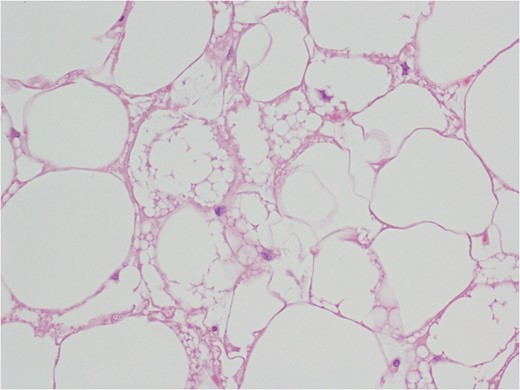

After multidisciplinary team discussion, surgical resection of the mass was planned: through a Pfannestiel incision a retroperitoneal dissection was performed, until exposition of the overmentioned mass, which was completely enucleated. During the operation, the absence of tumor infiltration of the surrounding structures was confirmed. No intraoperative histopathologic examination was carried out and the lesion was sent for definitive pathological examination. Macroscopically, the tumor presented as a well circumscribed encapsulated soft mass without infiltrative growth and/or satellite nodules. Tumor size was 15 × 7.5 × 6.5 cm3 and the weight was 309 g. External surface was smooth and the section had a lobulated aspect with a yellow-brown color. The histopathology examination revealed an adipocyte proliferation with moderate volume variation. Two populations of adipocytes were identified: one cluster with small, bland nuclei and the other with round to oval nuclei, with vacuolated eosinophil cytoplasm. In addition, rare multinucleated giant cells were observed. No cellular atypia was present. Immunohistochemistry was positive for S-100 and negative for MDM-2 (murine double-minute type 2) (Figs 7–9). Postoperative course was uneventful and the patient was discharged after 2 days.